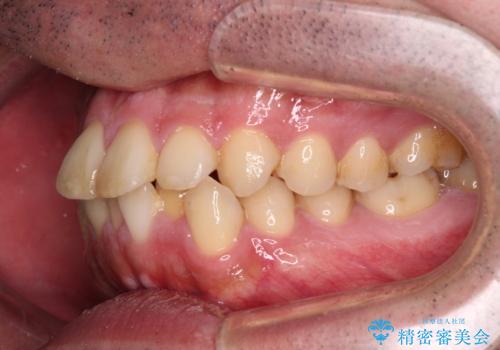

- 前歯のデコボコを治したいとのことで来院された患者様です。

できる限り楽して、短期間で治したいとのことで、ワイヤー装置にて矯正治療を行うこととしました。